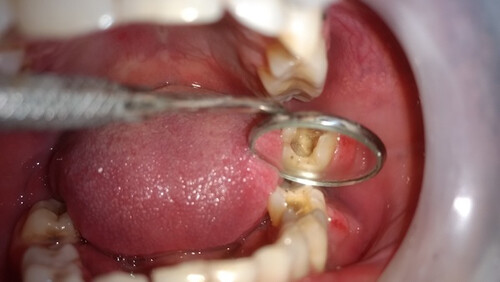

Клинический осмотр выявил наличие десневой ткани через отверстие доступа на нижнечелюстном левом первом моляре, что произошло в частной клинике (рис. 1). При рентгенографическом обследовании на левом первом моляре нижней челюсти была обнаружена перфорация на дистолингвальной стороне дна пульпы. На соседнем премоляре также присутствовал проксимальный кариес (Рисунок 2).